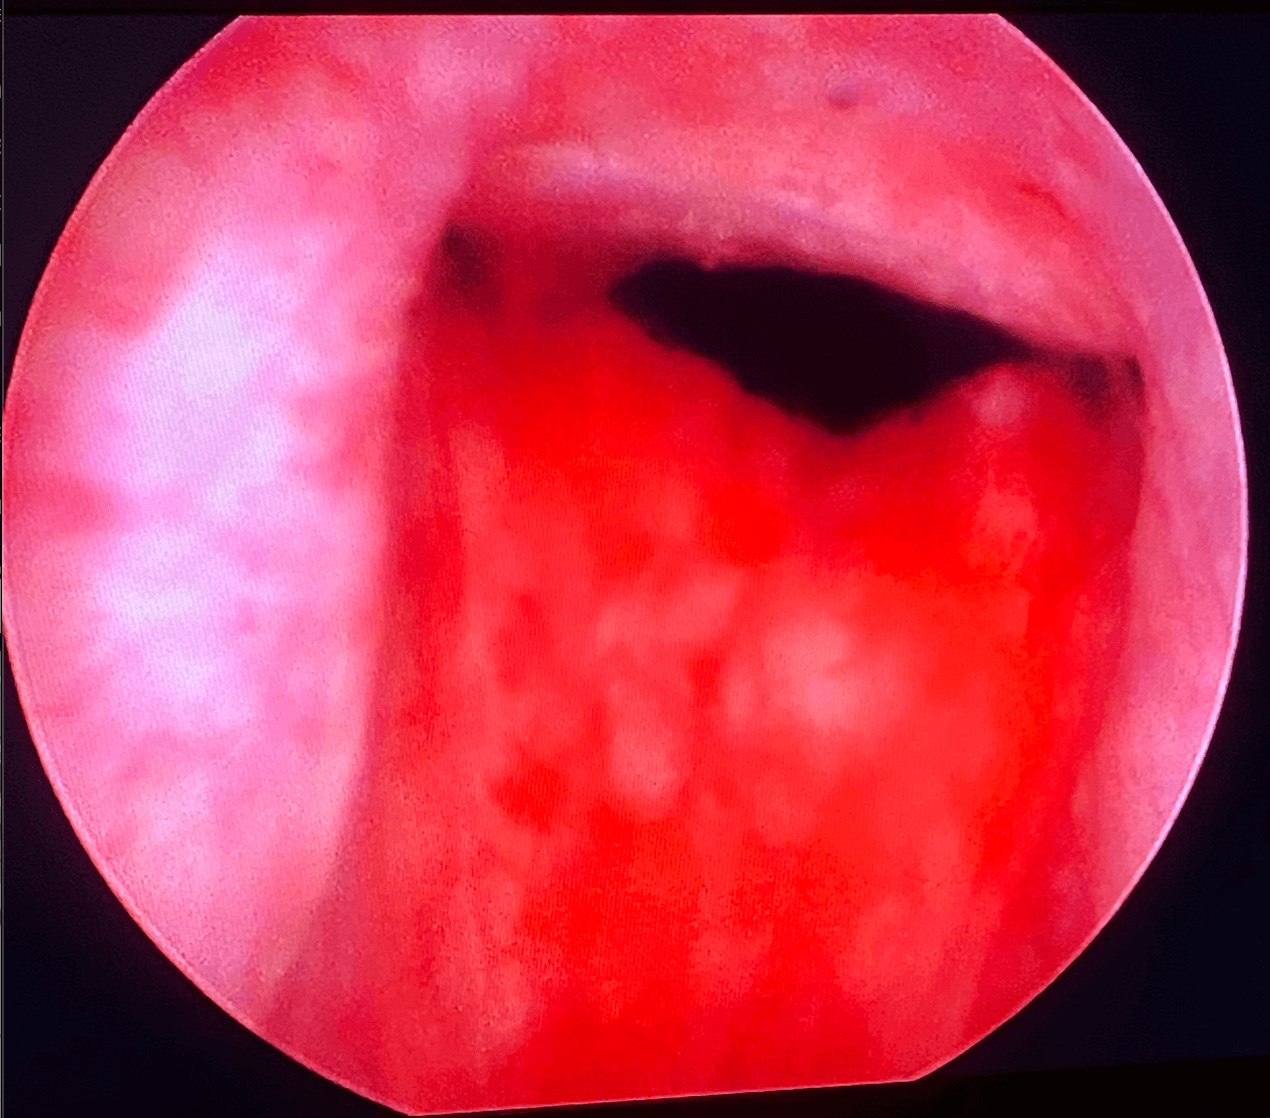

Atlanta males gets UroLift procedure

Procedure